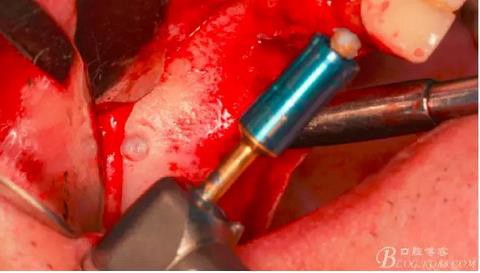

先使用1mm停止環(huán)套在開孔鉆上。

在需要開窗的位置的中心位點垂直骨面鉆入1mm深度。

沒有鉆透,更換2mm停止環(huán)。

轉(zhuǎn)速800-2000轉(zhuǎn),鉆透骨壁,有明顯落空感。有老師質(zhì)疑這么快的轉(zhuǎn)速會不會刺穿上頜竇膜?請大家放心,絕對不會。

此時頰側(cè)竇膜與骨壁已經(jīng)分離,無需擔(dān)心開窗損傷竇膜。使用環(huán)切鉆以小洞口為中心開窗,轉(zhuǎn)速500轉(zhuǎn),為了保證安全,可以將種植機調(diào)成反轉(zhuǎn)模式,一樣有強大的切割效率。